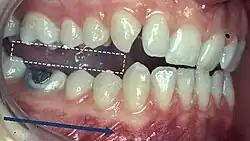

When describing the relationship between maxillary and mandibular incisors, the following categories make up Angle's incisal relationship classification:

- Class I: Mandibular incisors contact the maxillary incisors in the middle third or on the cingulum of the palatal surface

- Class II: Mandibular incisors contact the maxillary incisors on the palatal surface, in the gingival third or posterior to the cingulum. This class may be further subdivided into division I and division II:

- Class III: Mandibular incisors occlude with the maxillary incisors on the palatal surface, in the incisal third specifically or anterior to the cingulum

- In some cases the overjet is reversed (<0mm) and the mandibular incisors lie anterior to the maxillary incisors

- Class I: The mandibular first molar occludes mesially to the maxillary first molar, with the mesiobuccal cusp of maxillary first molar occluding in the buccal groove of mandibular first molar

- Class II: The mesiobuccal cusp of the maxillary first molar occludes anterior to the buccal groove of the mandibular first molar

- Class III: If the mesiobuccal cusp of the maxillary first molar occludes posterior to the buccal groove of the mandibular first molar[8]

Any deviation from the normal relation of teeth (Class I) is considered a malocclusion.